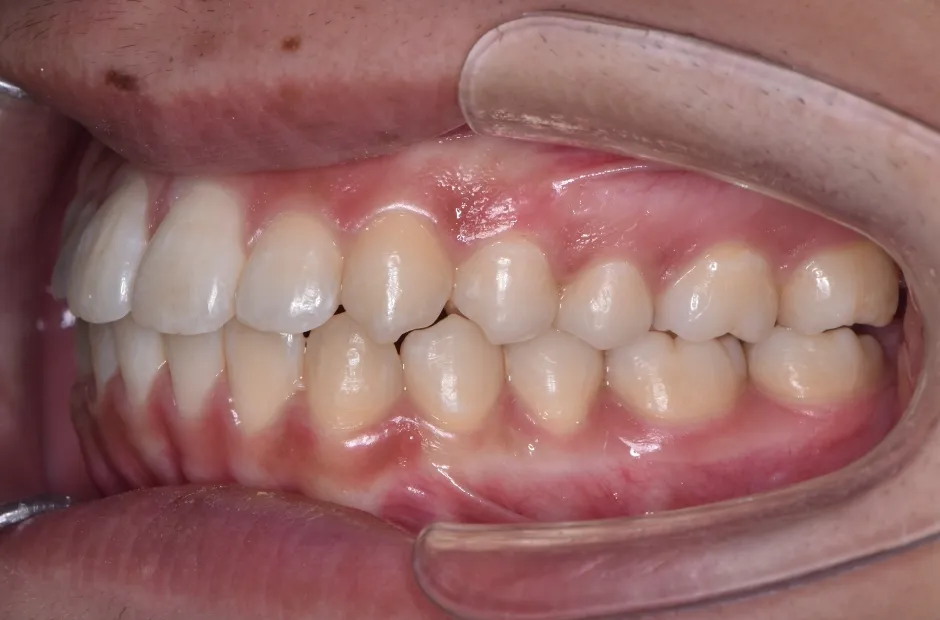

| 診断名・主訴 | 下顎前突、叢生 |

|---|---|

| 年齢・性別 | 23歳・女性 |

| 治療期間・回数 | 3年 |

| 治療に用いた主な装置 | 上顎5,5 下顎4,4 |

| 抜歯部位 | 舌側矯正 |

| 治療費 | 100万円(税抜) |

| リスク・副作用 | 装置による違和感・疼痛・歯肉退縮・歯根吸収・虫歯のリスクなど |

治療後